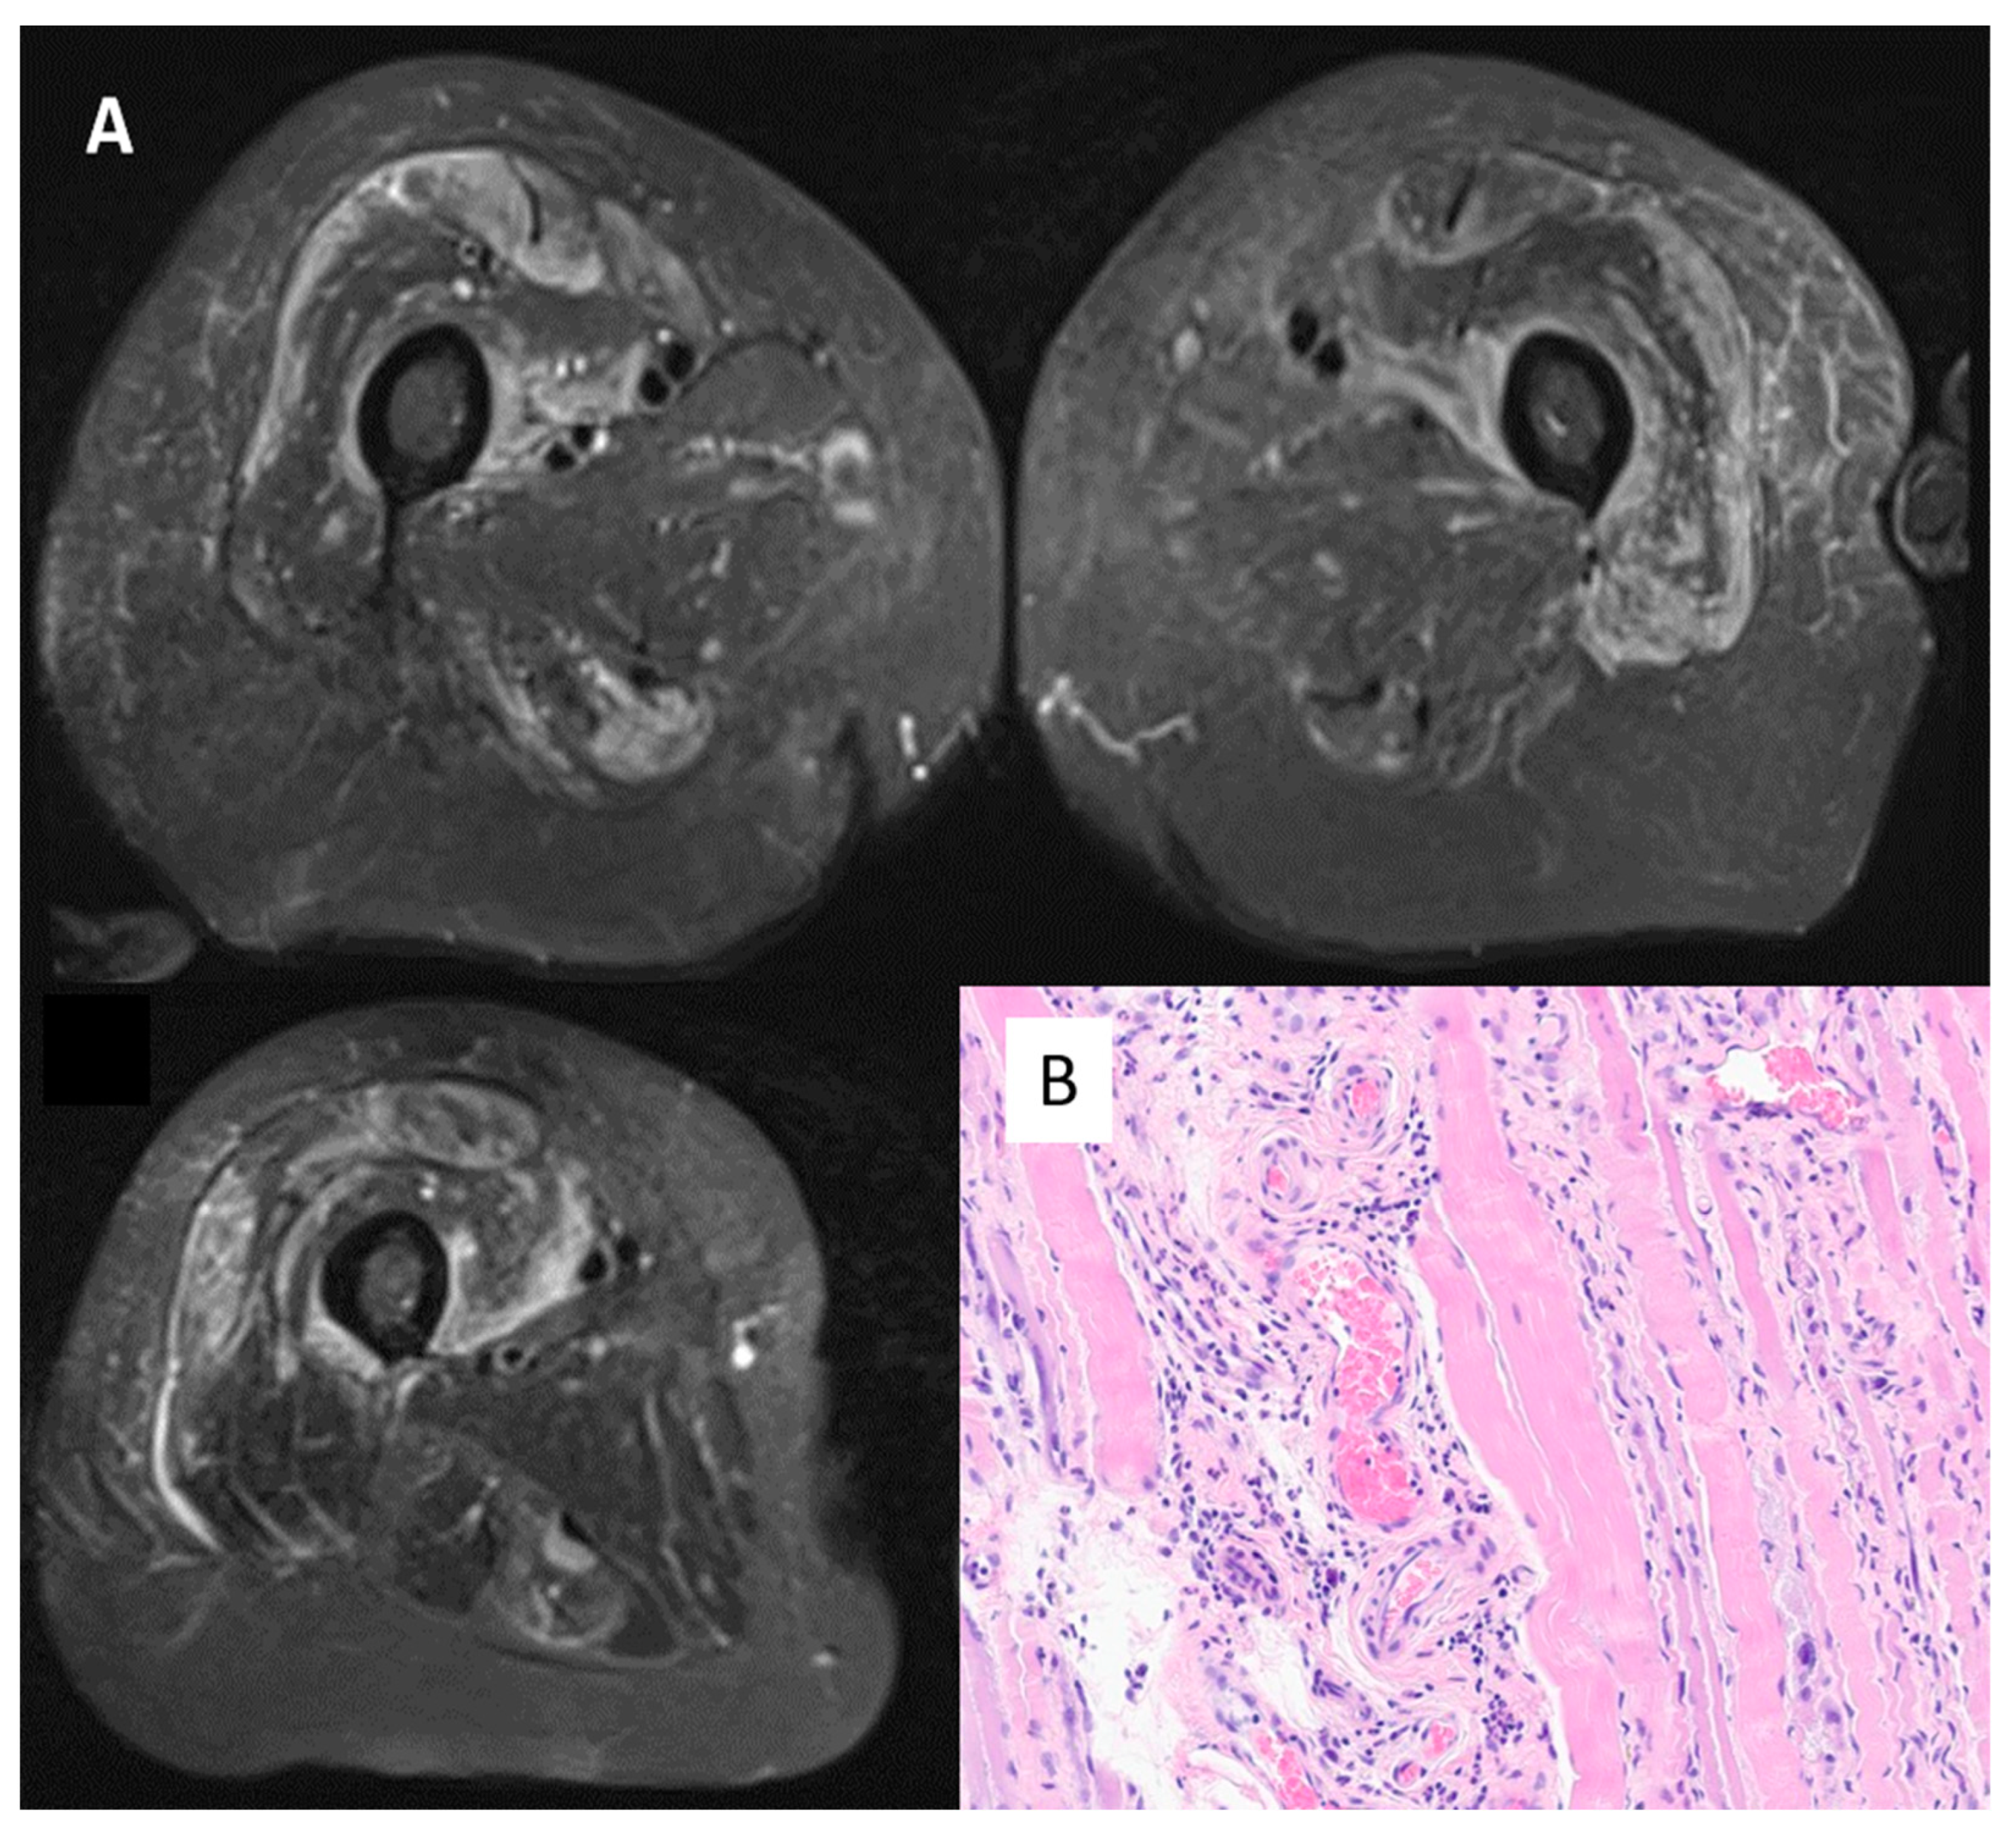

| Case 6 | No | AZD1222/ChAdOx1 | Asthenia, myalgia. CK 7598 U/L, CRP normal, myositic pattern on EMG, muscle oedema on MRI, biopsy positive ANA negative Myoblot + (Pl12 and Scl100) | No | Steroids, then azathioprine and one IV drip of immunoglobulins |

| Bradford | dose 2, February 2021 | ||||

| Female, 76 | (5 weeks) | ||||

| Case 7 | No | BNT162b2 | Asthenia, myalgia. CK 15,212 U/L, CRP 13 mg/L, muscle oedema on MRI, necrosis-related features on biopsy ANA negative, Myoblot negative Anti-HMGCR + | No | Steroids, then two IV drips of immunoglobulins |

| Bradford | dose 3, November 2021 | ||||

| Male, 64 | (5 weeks) | ||||

| Case 8 | No | BNT162b2 | Asthenia, myalgia. CK 8038 U/L, CRP normal, muscle oedema on MRI ANA negative, Myoblot negative | No | Physiotherapy |

| Bradford | dose 2, May 2021 | ||||

| Male, 70 | (24 weeks) | ||||

| Case 9 | Systemic lupus erythematosus (CK normal, no clinical myositis) | AZD1222/ChAdOx1 | Asthenia, myalgia. CK 1299 U/L, CRP normal, myositic pattern on EMG, muscle oedema on MRI, biopsy positive ANA + (Ro/RNP/Sm/ribosomal) | No (Immune thrombocytopenic purpura causing stroke) | Oral steroids and methotrexate |

| Bradford | dose 1, January 2021 | ||||

| Female, 37 | (4 weeks) | ||||

| Case 10 | No | BNT162b2 | Asthenia. CK 3581 U/L, CRP 109 mg/L, myositic pattern on EMG, muscle oedema on MRI, biopsy positive ANA negative, Myoblot negative Anti-HMGCR + | Mild interstitial changes on computed scan, asymptomatic | IV, then oral steroid Methotrexate |

| Mid-Yorkshire | Dose 3, October 2021 | ||||

| Female, 71 | (5 weeks) | ||||